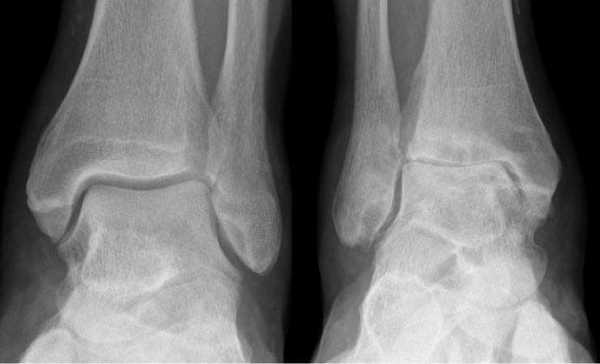

Артроз левого сустава. Суставная щель очень мала.